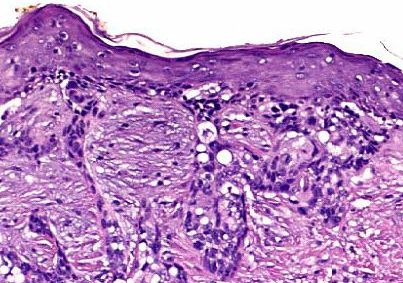

Sebaceous cell carcinoma. The tumour cells are the vacuolated cells in the

dermis and the epidermis. The appearance is the result of removal of oil

from the cytoplasm.

Magnified views of the vacuolated sebaceous cell carcinoma.

• Slides not treated with special stains. The slides may contain foamy cells or cells with vacuolated cytoplasm. The vacuolated cytoplasm indicates that the fat in the cytoplasm has been removed by alcohol during paraffin fixation.